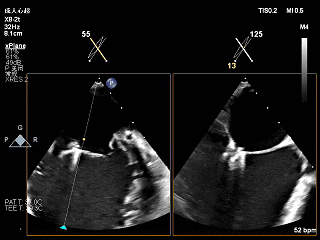

夹子释放后,2D下color,反流降至轻度

夹子释放后3D下观察组织桥稳定,反流降至trace

夹子释放后压差为2mmHg

肺静脉逆流明显改善